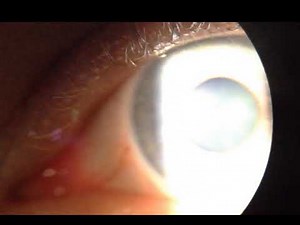

of Pupil - Vermiform

Pupil - Vermiform

- Vertilliform Movement

of Pupil - Eye Candy